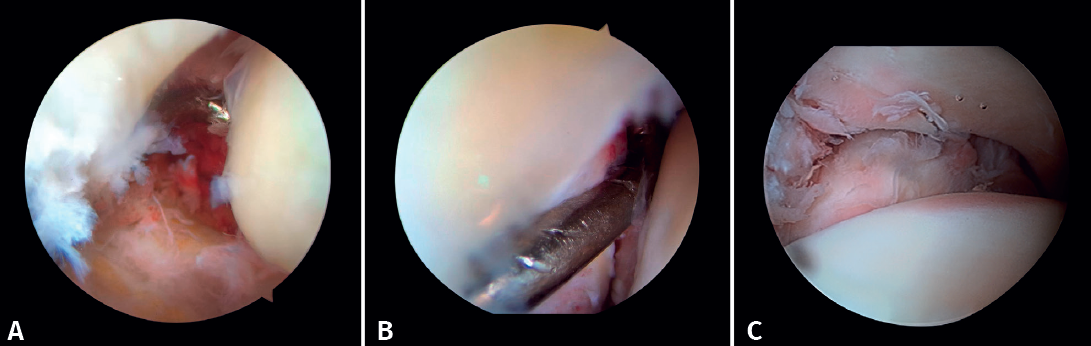

If possible, we reinsert unstable osteochondral fragments (Figure 3). In chondral lesions where it is not possible to reinsert the fragment, cartilage repair stimulation techniques can be used(5,13).

Figure 3. A: loose bodies; B: osteochondral lesion; C: reduction of the osteochondral lesion; D: medullary stimulation.